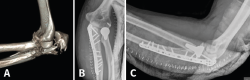

Fracturas de la apófisis coronoides

Las fracturas de coronoides aisladas son raras. De hecho, se ha visto que fracturas con tamaños y formas específicas van asociadas a patrones específicos de inestabilidad aguda de codo. Así, en función de la morfología de la fractura, podremos sospechar determinadas lesiones y anticipar la planificación quirúrgica(46). Será imprescindible la TAC con reconstrucción 3D para visualizar esos fragmentos.

Figura 10. Correspondencias entre la clasificación de Regan y Morrey, y la clasificación de O’Driscoll.

O’Driscoll propuso una clasificación basada además en la localización y el número de fragmentos (Tabla 5). Posteriormente, observaron que en función del tamaño y la localización de los fragmentos existían asociaciones con otras lesiones y definieron 3 tipos de patrones(47,48,49,50):

- Fractura de la punta de la coronoides asociada a luxación de codo y a fractura de la cabeza del radio, la llamada tríada terrible. Se ven normalmente tras una luxación posterior o posterolateral. Se pensaba que la fractura coronoides era por avulsión, pero en realidad es por cizallamiento. Si asocia una lesión del LCL, puede llevar a una inestabilidad rotatoria posterolateral (Figura 11).

Figura 11. A: imagen en 3D de una fractura de tipo I de O’Driscoll con inestabilidad de codo, donde se observa además un fragmento de la cabeza del radio desplazado; B: imagen de tomografía axial computarizada (TAC) en un plano sagital. C: imagen de reconstrucción en 3D de una fractura de tipo II.